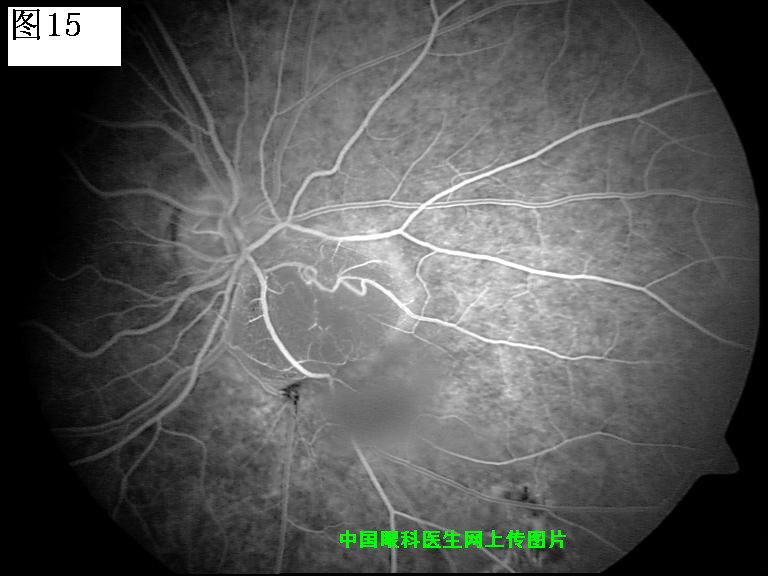

13 14 15 16